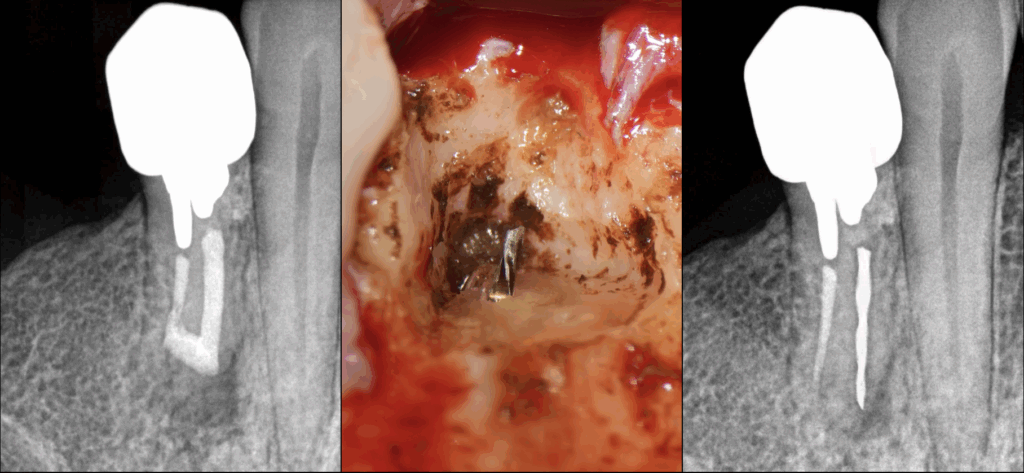

🦷 Instrument fracturé & chirurgie endodontique

👉 Les avantages de la microchirurgie endodontique dans ce cas :

✅ 𝐏𝐫𝐞́𝐝𝐢𝐜𝐭𝐢𝐛𝐢𝐥𝐢𝐭𝐞́ 𝐝𝐞 𝐥𝐚 𝐝𝐞́𝐩𝐨𝐬𝐞 𝐢𝐧𝐬𝐭𝐫𝐮𝐦𝐞𝐧𝐭𝐚𝐥𝐞

🛡️ 𝐂𝐨𝐧𝐬𝐞𝐫𝐯𝐚𝐭𝐢𝐨𝐧 𝐦𝐚𝐱𝐢𝐦𝐚𝐥𝐞 𝐝𝐞𝐬 𝐭𝐢𝐬𝐬𝐮𝐬 𝐝𝐞𝐧𝐭𝐚𝐢𝐫𝐞𝐬

(➡️ pas de dépose corono-radiculaire, pas de délabrement canalaire orthograde pour tenter de déposer ou by-passer l’instrument)

🔍 𝐆𝐞𝐬𝐭𝐢𝐨𝐧 𝐝𝐞 𝐥’𝐢𝐬𝐭𝐡𝐦𝐞 𝐣𝐨𝐢𝐠𝐧𝐚𝐧𝐭 𝐥𝐞𝐬 𝐜𝐚𝐧𝐚𝐮𝐱 V & L